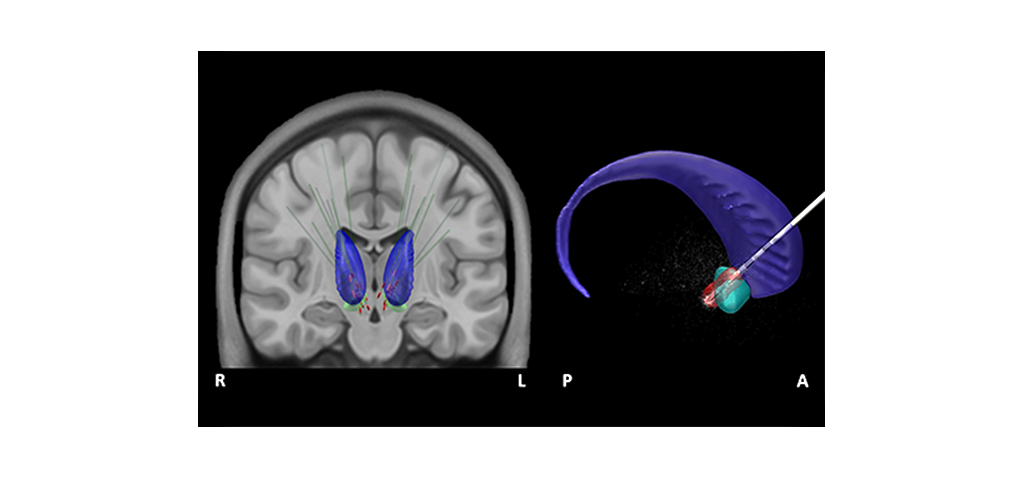

Investigadores de la Universidad de Cádiz, adscritos al Instituto de Investigación Biomédica de Cádiz (INiBICA), han participado en un estudio publicado en la prestigiosa revista Cerebral Cortex (Oxford University Press), en el que se ha constatado que la estimulación del núcleo accumbens favorece el control inhibitorio en pacientes con Trastorno Obsesivo Compulsivo (TOC), gracias a la reactivación de la corteza prefrontal derecha.

Para entender mejor este trabajo, en el que también han participado también expertos de la Universidad Politécnica de Madrid y el Hospital Clínico San Carlos de Madrid, hay que tener en cuenta que el núcleo accumbens en nuestro cerebro tiene una gran influencia a la hora de integrar aspectos cognitivos, motivacionales y motores, y es uno de los principales núcleos que permite que la voluntad se traduzca en acción y se realicen conductas de búsqueda de placer. Tal como se refleja en los resultados de este artículo, los científicos han observado que los pacientes con TOC, cuando se les aplica una Estimulación Cerebral Profunda de esta zona cerebral, son capaces de frenar y modular la conducta impulsiva característica de esta patología. El Trastorno Obsesivo Compulsivo es una afección mental que se caracteriza por tener pensamientos incontrolables y recurrentes que generan ansiedad o aprensión y pueden provocar comportamientos repetitivos, con gran repercusión en la vida de las personas que lo sufren.

Para desarrollar la investigación, los investigadores evaluaron a nueve pacientes diagnosticados con TOC de tipo refractario (resistentes a tratamientos previos incluido el psicofarmacológico) y tratados con Estimulación Cerebral Profunda en el núcleo accumbens. Es decir, utilizaron dispositivos cerebrales implantados en esa zona de manera permanente, llamados neuroestimuladores, para alterar la actividad eléctrica cerebral, “con el objetivo de modular a gran escala la actividad anómala cortico-subcortical, que se cree responsable del control inhibitorio y la conducta obsesiva en estos pacientes”.

Por otro lado, los investigadores también detectaron “que el aumento de la re-activación de este circuito cerebral se asoció a un mayor grosor de la corteza cerebral en áreas prefrontales”. De hecho, estos resultados corroboran “el papel fundamental de una Estimulación Cerebral Profunda del núcleo accumbens para modular la actividad del circuito neural responsable de la sintomatología característica de pacientes con TOC, lo que podría producirse fundamentalmente por la reorganización de la actividad funcional en la zona prefrontal derecha”, como explican estos expertos.